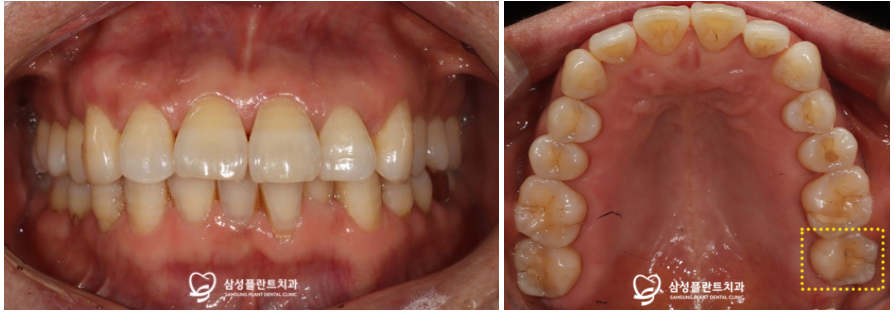

추후 임플란트가

뼈와 잘 결합되는 기간을 거친 뒤

2차 수술을 진행하였고,

이후 본을 떠서 임시치아를 장착해드렸습니다.

임시치아를 약 한달간 사용하면서

불편함이 없는지 확인한 후,

최종 보철물 셋팅까지 잘 마무리해드렸습니다!

환자분께서 한동안 왼쪽으로

아예 식사를 못하셨는데,

이제 불편함이 모두 사라졌다며

만족해하셨답니다.